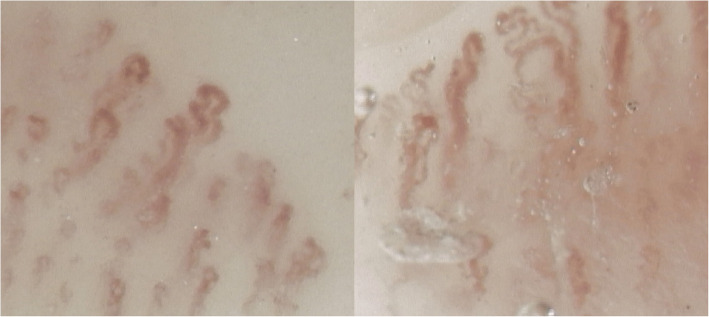

This case report describes the clinical course of a 78-year-old patient diagnosed with polycythemia vera (PV), who presented with pronounced acrocyanosis of the hands in 2021. The patient was treated with hydroxyurea (oncocarbide), and nailfold capillaroscopy revealed an "abnormal pattern" characterized by pronounced architectural disarray and capillary tortuosity, which is uncommon in patients with myeloproliferative neoplasms (MPNs). In 2023, owing to suboptimal symptom management and hematological side effects, the treatment was switched to ruxolitinib, which led to significant clinical improvements by 2024, including near-complete resolution of acrocyanosis and substantial improvement in capillaroscopic abnormalities, with only residual capillary tortuosity noted. This case emphasizes the need for individualized therapeutic interventions for PV, and underscores the potential role of ruxolitinib in ameliorating microvascular dysfunction.